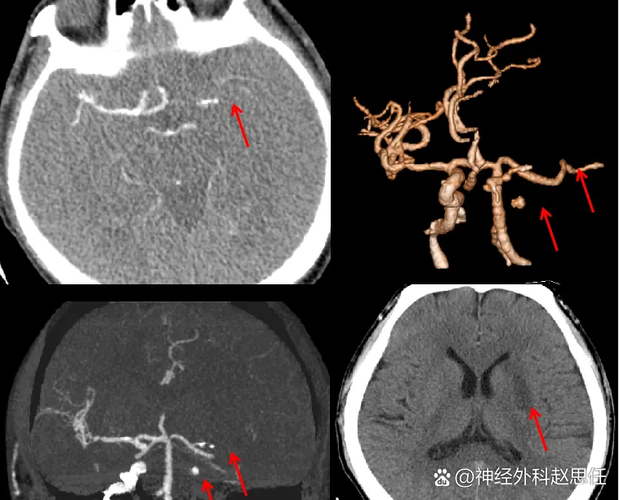

- “主干道”:这是最关键、最危险的部分,大脑的血液供应主要有四条主干道:两条颈内动脉和两条椎动脉,它们汇合形成“大脑中动脉”,是供应大脑半球最主要的血管,所谓“主干道梗死”,通常指的就是一侧大脑中动脉的起始部或主干被完全堵塞。

- “梗死”:指脑组织已经因缺血发生了不可逆的坏死。

患者的左侧大脑最主要的供血血管被堵死了,导致大片脑组织正在迅速死亡。